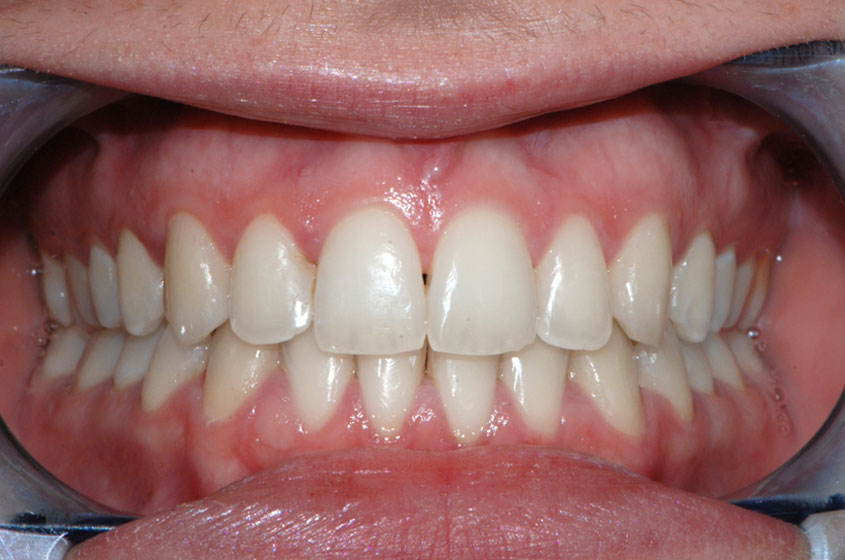

https://sorridibene.etweb.it/wp-content/uploads/2020/07/3-1.jpg

Affollamento dentale

In una occlusione normale ogni dente occupa uno spazio ben preciso in arcata. Se i denti non sono correttamente allineati e...